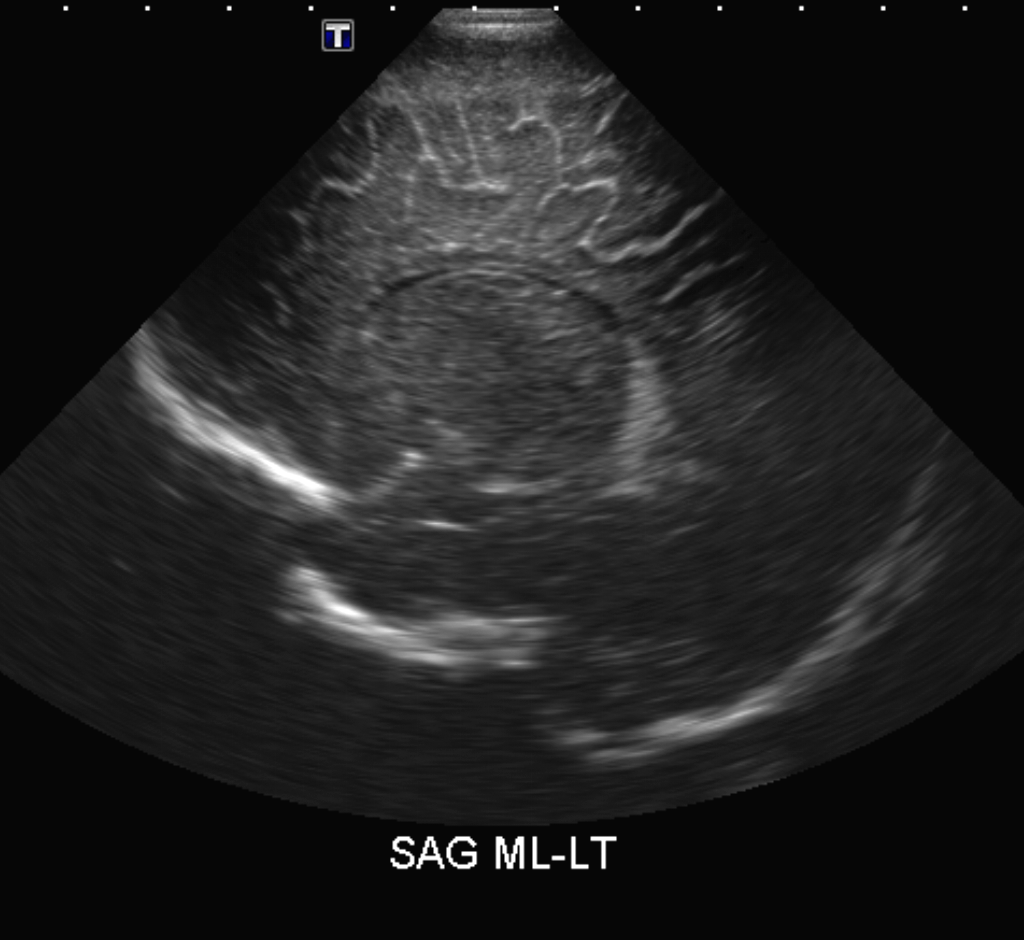

CSF spaces/ventricular system

There is a prominence of the extra axial fluid spaces. [Yes/No]

There are debris/septations in the extra axial fluid spaces. [Yes/No]

There are debris/septations in the ventricles. [Yes/No]

There is a subdural collection on the right/left side. [Yes/No]

There is prominence of the ventricular system. [Yes/No]

There is an asymmetry of the ventricular system. [Yes/No]

The choroid plexus is bulky/lobulated. [Yes/No]

There is a choroid plexus cyst measuring… [Yes/No]

There are debris/clots in the occipital horn. [Yes/No]

There is a posterior fossa cyst measuring… [Yes/No]

The tentorium is elevated/depressed. [Yes/No]

The lateral ventricle/s are dilated. [Yes/No]

The 4th ventricle is dilated. [Yes/No]

There are pseudo cysts. [Yes/No]